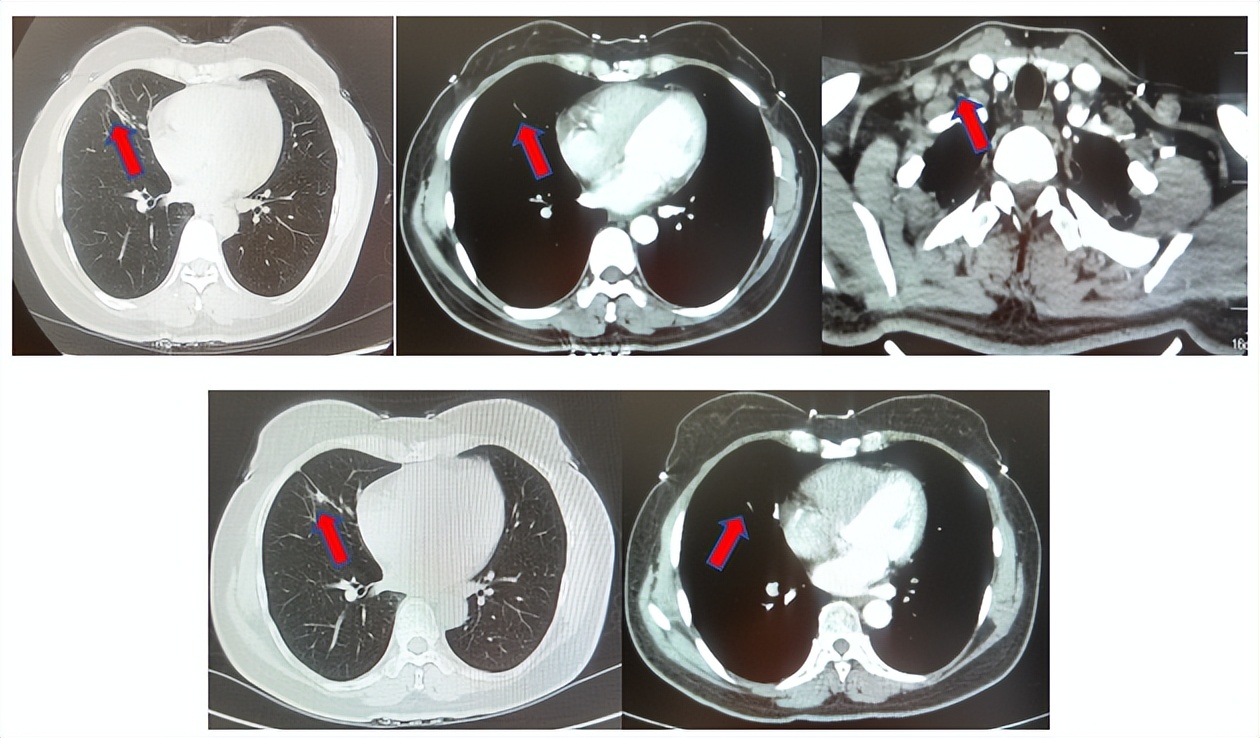

患者符合我科正在开展的“一项比较Durvalumab治疗与标准治疗(含铂化疗)用于PD-L1高表达晚期非小细胞肺癌患者一线治疗的III期随机、开放、多中心研究”的入组要求,经知情同意进入该试验,经随机进入化疗组,于2017年7月至2023年12月应用培美曲塞联合卡铂治疗6周期,后行培美曲塞单药维持治疗105周期,肺内CT现实右肺下叶病灶缩小90%,颅内病灶缩小100%,最佳疗效肺内病灶PR及颅内病灶达CR(图2),于2023年2月复查CT,肺内病灶逐渐增大,至2024年1月,疾病进展出组该临床试验,一线无进展生存为78个月。

图2:上两图分别展示2021年5月患者达到最佳疗效时肺CT肺窗及纵隔窗肺内病灶及肺门淋巴结影像,下三图表示最佳疗效时脑MRI影像

患者进入到二线治疗,该患者再次符合我科“优替德隆对照多西他赛治疗含铂化疗失败的局部晚期或转移性非小细胞肺癌的III期、开放、随机对照临床试验”经随机进入多西他赛组,截止至目前患者已行多西他赛治疗19周期,期间评效为SD(图3),二线无进展生存至今为14个月,患者总生存期截止目前超过92个月(整体治疗过程如图4所示)。

图3:上两图分别展示2024年1月患者一线进展时肺CT肺窗及纵隔窗肺内病灶影像,下两图表示2024年12月患者二线治疗间期评效时肺CT肺窗及纵隔窗肺内病灶影像